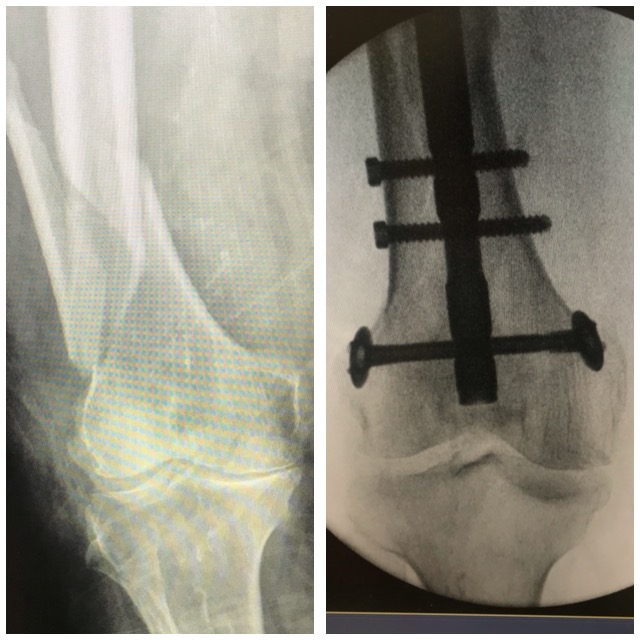

Polven

alueen murtuma

Ennen – jälkeen